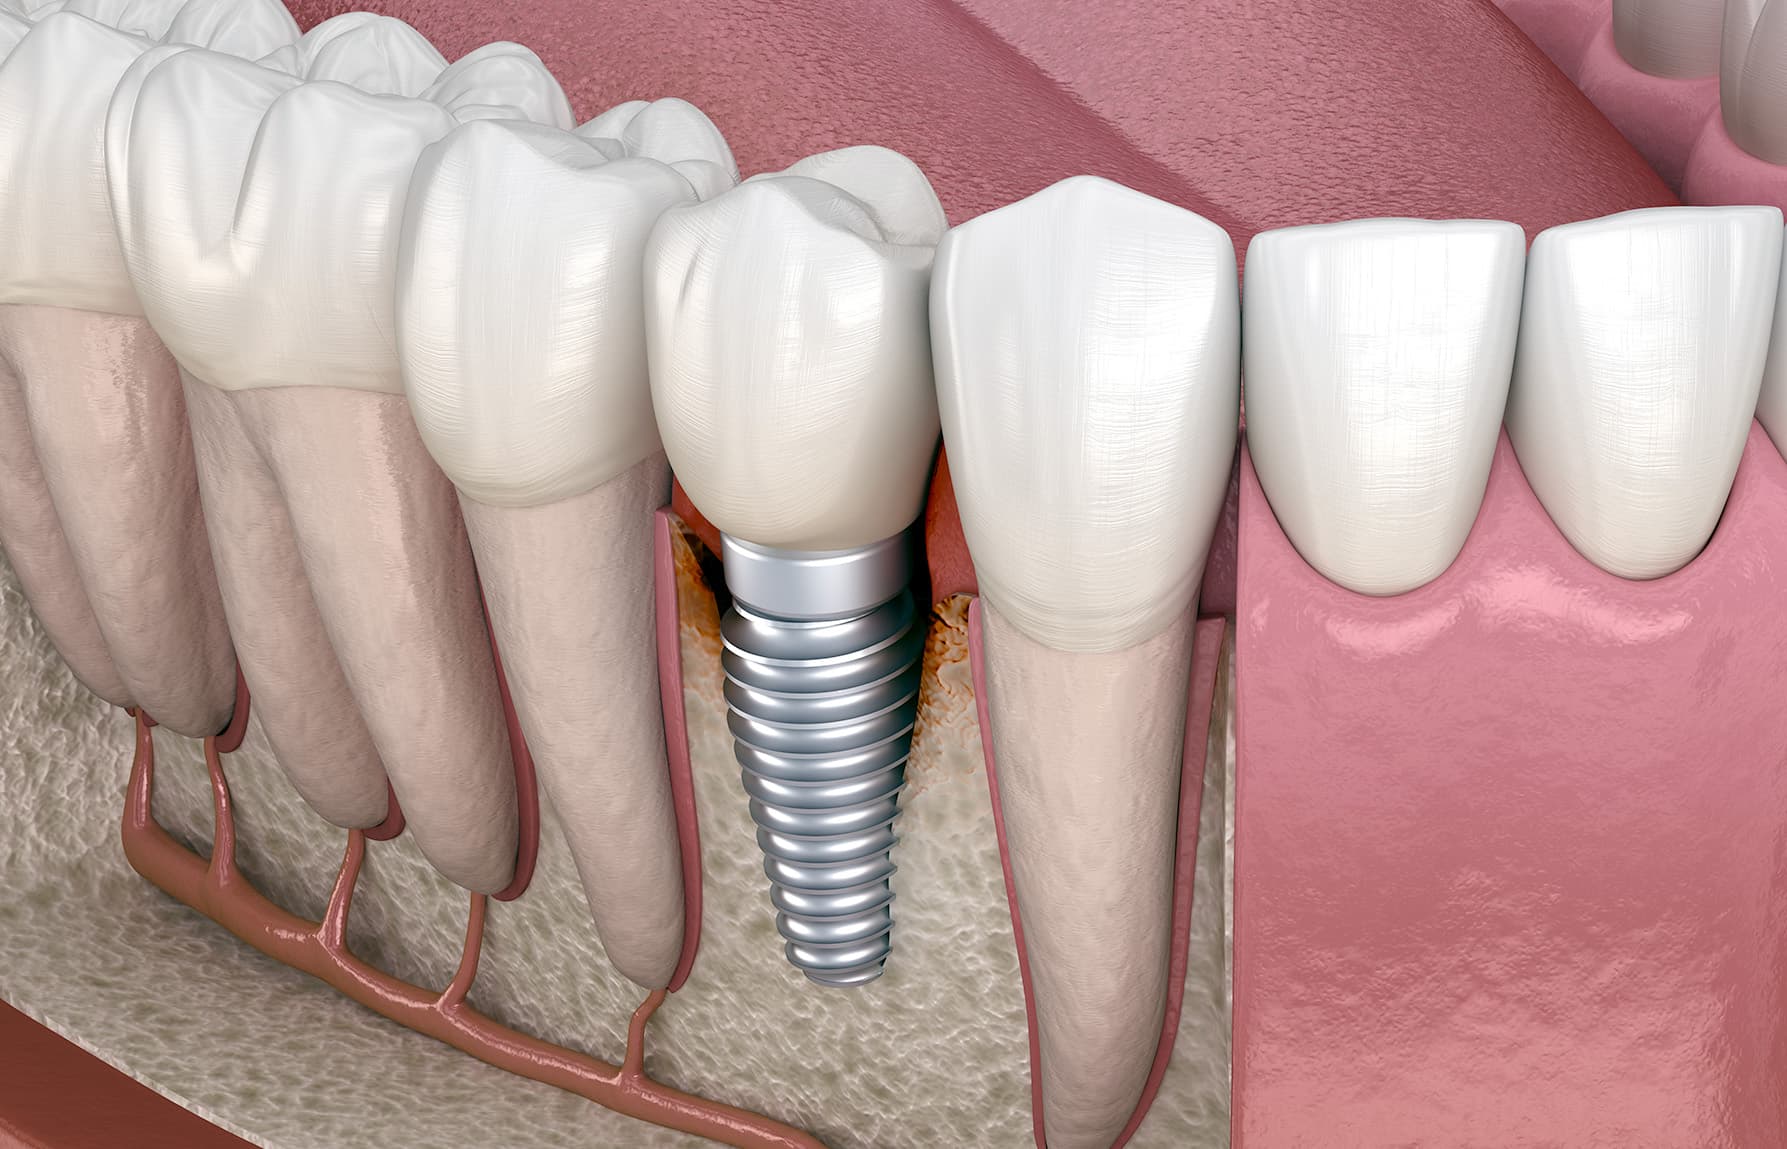

Tandimplantaten

Een tandimplantaat is een soort schroefje, gemaakt van titanium, dat het lichaam gemakkelijk accepteert. Het is een veilige en permanente vervanging van de tandwortel en wordt in de kaak aangebracht. Op het tandimplantaat wordt een kunstelement (bijvoorbeeld een kroon, een brug of een kunstgebit) geplaatst. In enkele maanden vormt zich nieuw botweefsel en tandvlees om het schroefje en is het tandimplantaat net zo stevig verankerd als een natuurlijke tandwortel.

- Bij vervanging van een enkele tand: kroon op implantaat.